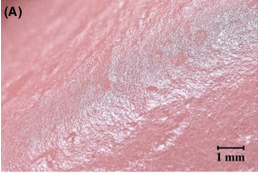

INFLUENCE OF CAD/CAM FABRICATION ON DENTUER SURFACE PROPERTIES

O. Steinmassl1 | H. Dumfahrt2 | I. Grunert2 | P.-A. Steinmassl2. Micro-organisms

colonising dentures have been linked to not only local mucosal inflammation,1 caries and periodontitis of residual teeth2 but also disseminated infections. Aspirated denture plaque has been shown to cause pneumonia3 and can therefore be a severe health threat for patients with decreased immunity.4

THE INFLUENCE OF POLISHING TECHNIQUES ON PRE-POLYMERIZED CAD/CAM ACRYLIC RESIN DENTURE BASES

Associate Professor, Department of Oral and Maxillofacial Prosthodontics, King Abdulaziz University, Jeddah, Kingdom of Saudi Arabia. Objective: The purpose of this study was to inspect the effects of mechanical polishing and chemical polishing on the surface roughness (Ra) and contact angle (wettability) of heat-cured, auto-cured and CAD/CAM denture

base acrylic resins.